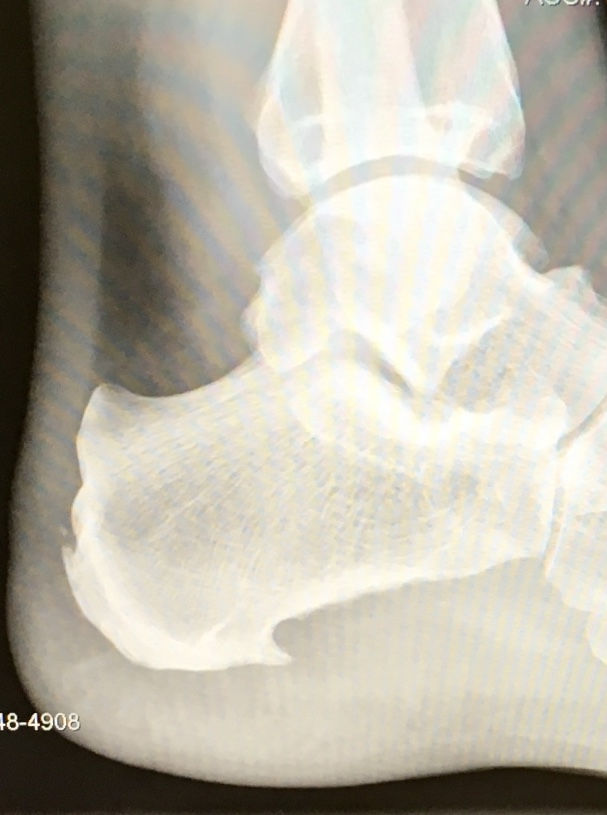

“Insertional Achilles’ debridement with FHL transfer” to remove the embedded bone spurs - successful!

Basically, this procedure is a complete detachment of the Achilles’ tendon, removing the bone spurs, and scraping the extra bone and calcification from the heel bone. Then the Flexus Hallucis Longus (FHL) tendon leading to the big toe, is cut and a hole is drilled into the heel bone, where the FHL is inserted and secured. The transfer of this tendon is used for strengthening and augmenting the repair. The FHL tendon also provides additional blood supply to speed the recovery.

Once the FHL tendon transfer is complete, several more holes are drilled into the heel bone. Special bio-absorbable inserts are hammered into the holes. These inserts use Arthrex repair thread to hold the Achilles’ tendon in place. After the inserts are in place, the Arthrex thread is used to tie the Achilles’ tendon back to the heel bone. Once all of the debris is removed and the tendons are secured, the final step is to flush and close the surgical area and place the foot in a cast or splint.